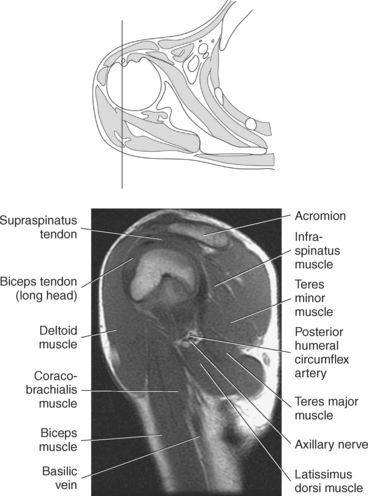

Muscles of the scapula are described in Table 9.2 and demonstrated in Figures 9.34 through 9.52. The large deltoid muscle originates on the clavicle, acromion, and scapular spine to blanket the shoulder joint as it extends to insert on the deltoid tuberosity of the humerus. This powerful muscle forms the rounded contour of the shoulder and functions primarily to abduct the arm (Figure 9.48). The teres major muscle is a flat rectangular muscle that adducts and medially rotates the arm. It extends from the inferior angle of the scapula to the medial aspect or lip of the intertubercular groove of the humerus (Figure 9.49, A). The four remaining muscles, supraspinatus, infraspinatus, teres minor, and subscapularis, closely surround the scapula and compose the rotator cuff (Figures 9.49 through 9.52). The rotator cuff provides dynamic stability to the shoulder joint and allows for adduction, abduction, and rotation of the humerus. The supraspinatus, infraspinatus, and teres minor muscles are located on the posterior aspect of the scapula. The tendons of these muscles insert on the greater tubercle of the humerus. The supraspinatus muscle lies in the supraspinous fossa of the scapula and helps to abduct the arm. The tendon of the supraspinatus muscle is the most frequently injured tendon of the rotator cuff because of possible impingement as it extends under the acromioclavicular joint and continues over the humeral head (Figure 9.49, B). The infraspinatus muscle is a triangular muscle that lies below the scapular spine in the infraspinous fossa. It acts to laterally rotate the arm (Figure 9.49, A). Lying along the inferior border of the infraspinatus muscle is the elongated teres minor muscle, which also acts to laterally rotate the arm (Figure 9.49, B). The subscapularis muscle is the only muscle of the rotator cuff located on the anterior surface of the scapula; its tendon inserts on the lesser tubercle of the humerus (Figures 9.50 through 9.52). The subscapularis muscle acts to medially rotate the humerus. See sequential images through the shoulder (Figures 9.34 through 9.47).

The primary arteries supplying the shoulder region include the axillary and brachial arteries (Figures 9.34 through 9.45 and 9.144, A). The axillary artery begins at the lateral border of the first rib as a continuation of the subclavian artery. It ends at the inferior border of the teres major muscle, where it passes into the arm and becomes the brachial artery. The axillary artery and its branches supply blood to numerous thoracic and shoulder structures, including the first and second intercostal spaces, axillary lymph nodes, mammary gland in women, and scapular, serratus anterior, pectoral, latissimus dorsi, deltoid, and triceps brachii muscles. The branches of the axillary artery typically include the superior thoracic, thoracoacromial, lateral thoracic, subscapular artery, and anterior and posterior humeral circumflex arteries. The brachial artery is the principal arterial supply to the arm. It courses inferiorly on the medial side of the humerus then continues anterior to the cubital fossa of the elbow. The brachial artery is relatively superficial and palpable throughout its course. It accompanies the median nerve, which crosses anterior to the artery in the middle of the arm. During its course, the brachial artery gives rise to numerous muscular branches, which include the profunda brachii, superior ulnar collateral, and inferior ulnar collateral arteries (Figure 9.144, A).